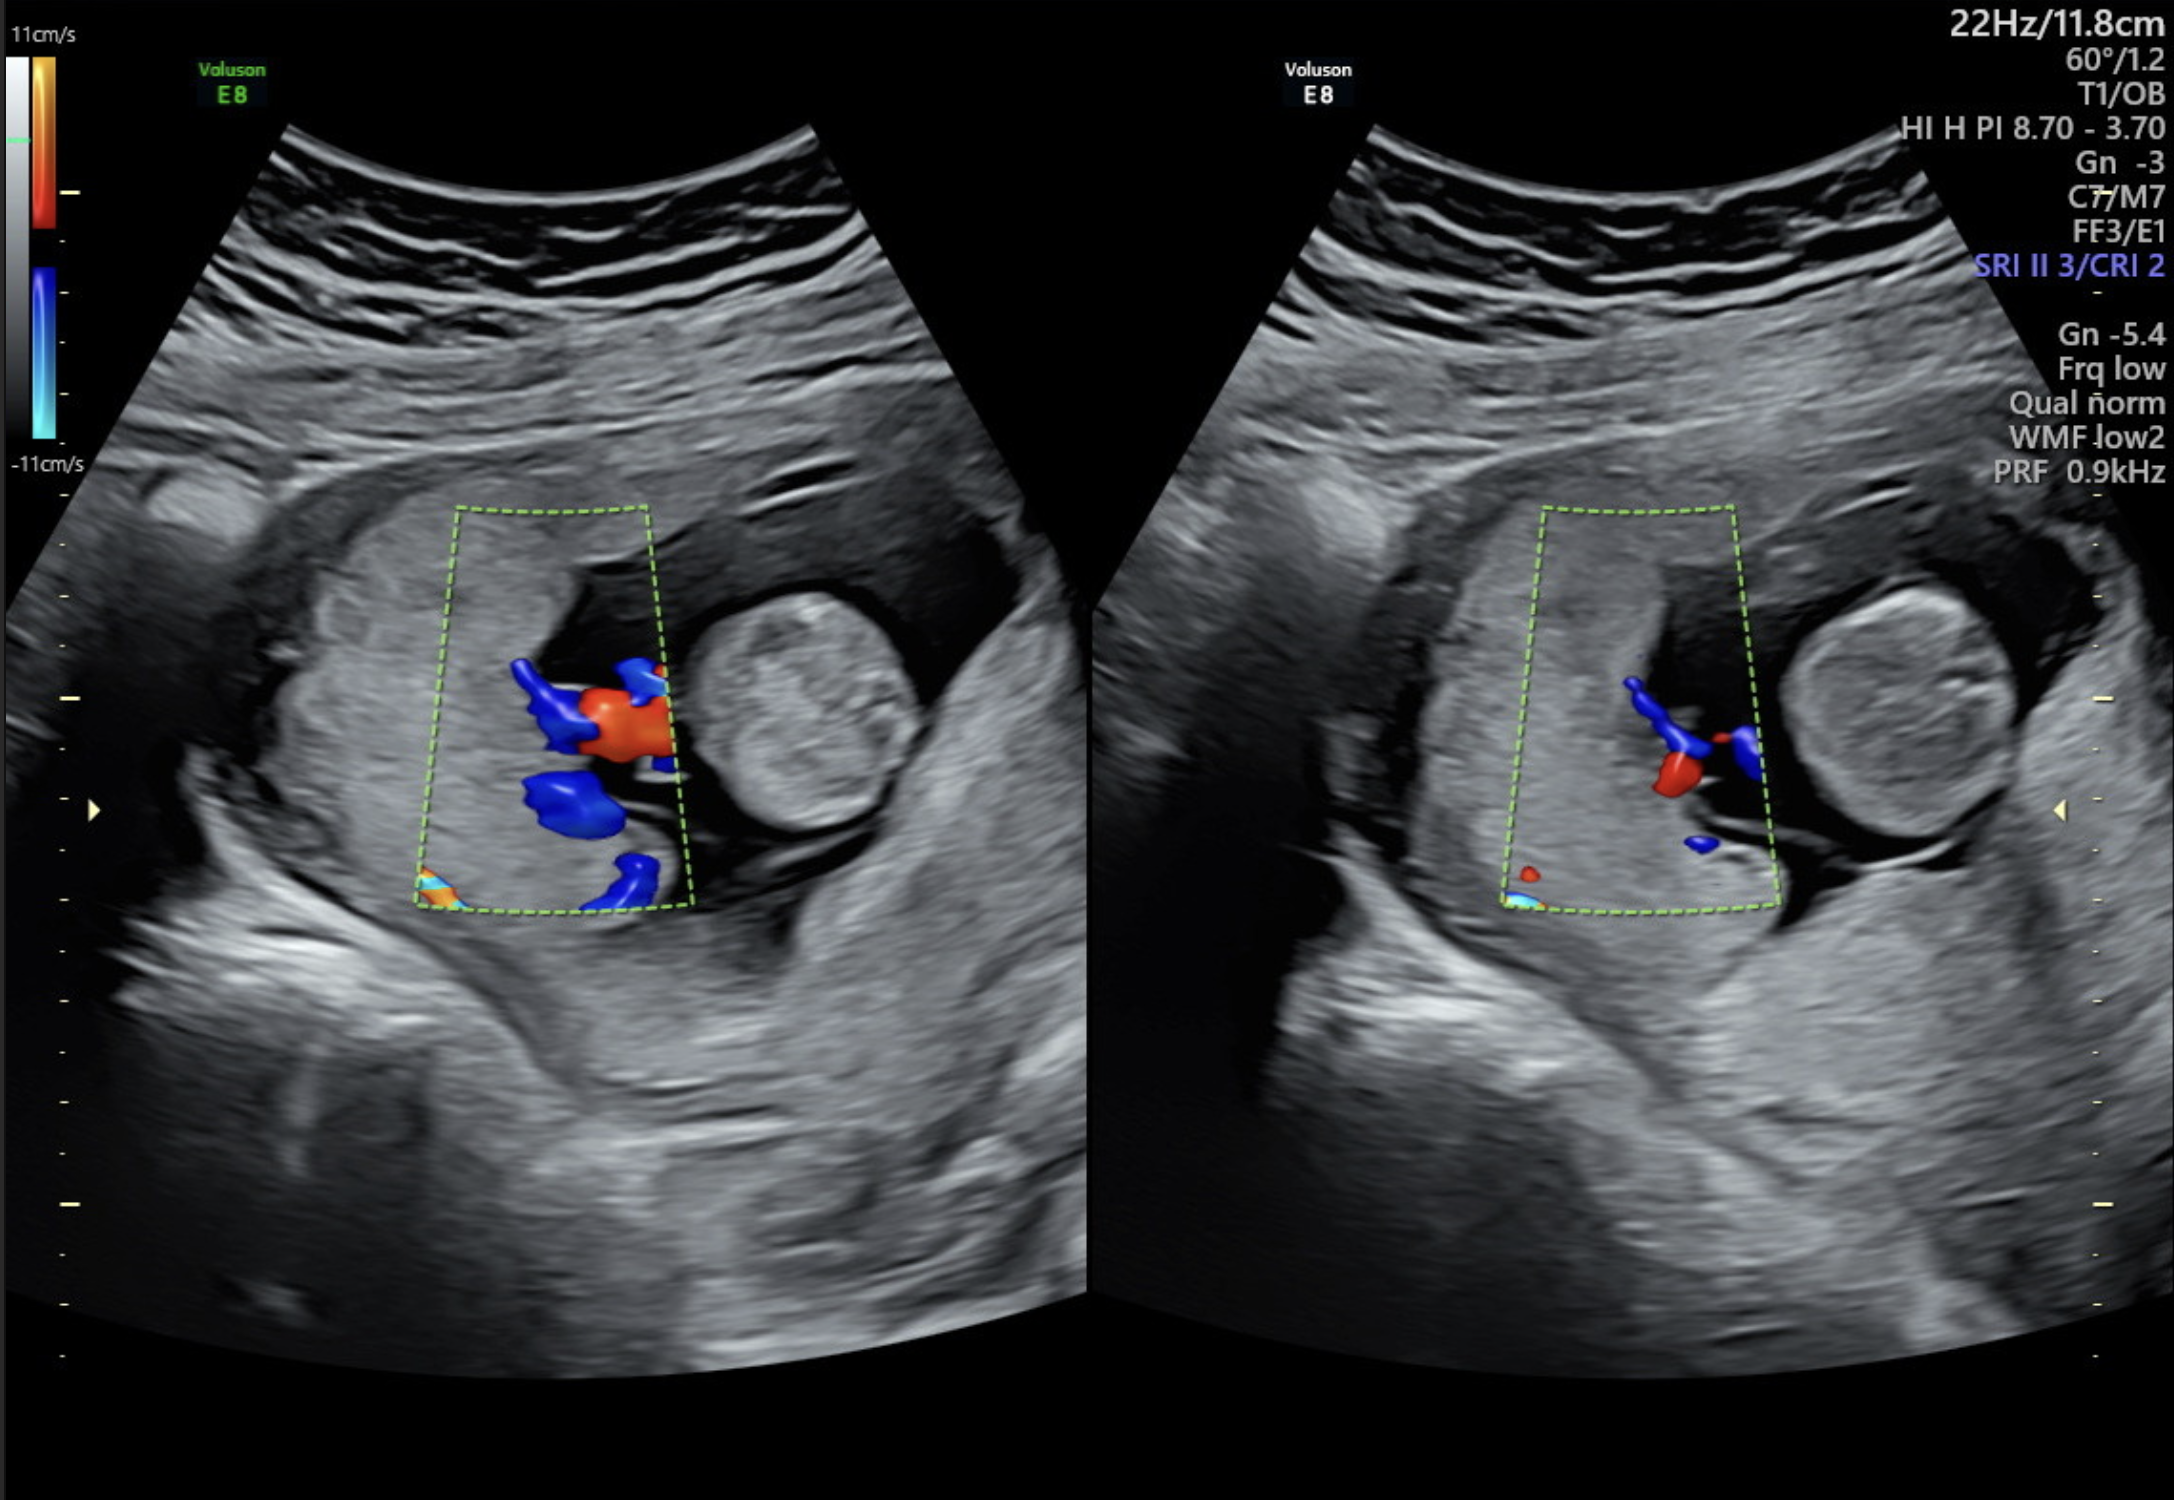

- Doppler ultrasound of the right and left uterine arteries